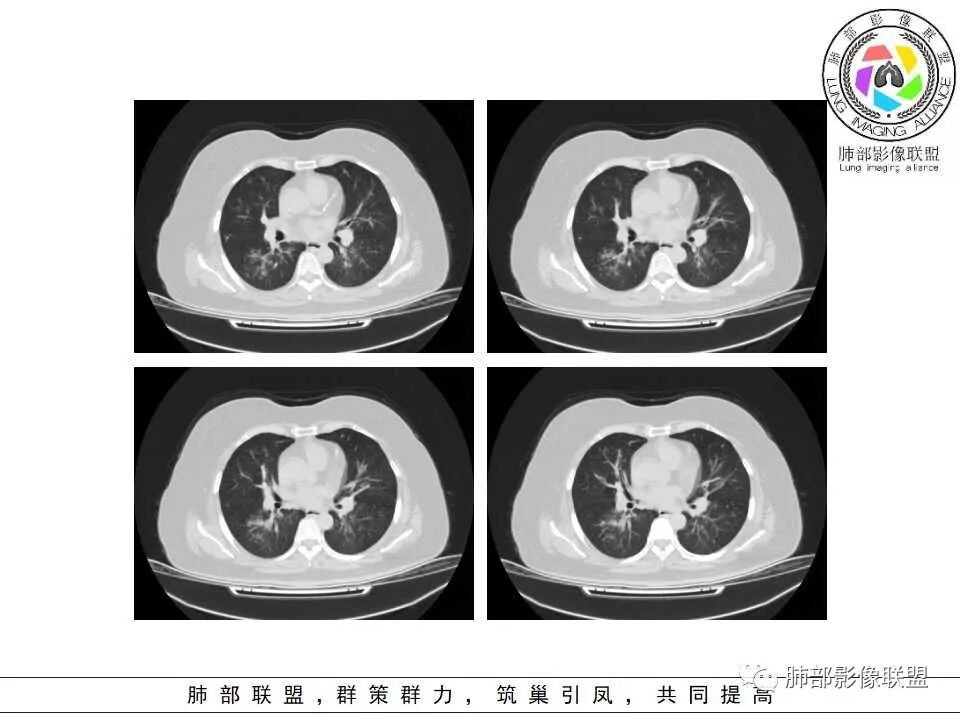

老年女性,发现白细胞升高两年,此次入院多次查外周血白细胞>30*10^9/L,淋巴降低,CRP显著升高,但病程中无发热,以细菌性炎不好解释;CT提示有脾大,结合外周血象,首先考虑存在血液系统疾病(白血病)基础,且未系统诊治;肺部CT提示双肺中轴间质增粗,伴随支气管管壁增厚?多发树丫及腺泡结节,部分呈点晕征,可见肺动脉分枝增粗,一元论考虑白血病肺部浸润;二院论考虑白血病并发气道侵袭曲霉。以患者病程进展看,更倾向于白血病肺部浸润。

肺动脉增粗,支气管有改变

左侧腔内有粘液栓,右侧支气管局部有扩张

肺动脉高压:性质待查,血象哪位老师解释一下,看右上支气管,怀疑以前都有过

1.病灶沿支气管分布的特点相当明显,相应支气管壁广泛增厚。这种与支气管关系极为密切的片影和/或结节影,常高度提示气道相关感染,如支气管肺炎。

2.患者两肺多发病变,具有广泛性。如此广泛分布更多见于免疫低下的机会性感染。

3.支气管壁广泛增厚对气道侵袭性曲霉病具有一定的提示意义。注意患者没有支气管扩张,临床也未提供IGE等实验室资料。

4.老年女性患者,咳嗽少痰,伴喘息气短8天。注意患者没有发热,中毒症状不明显。既往糖尿病、高血压病史。

炎性指标升高,头孢等药物覆盖疗效不佳。

白细胞升高异乎寻常,注意病史已有两年之久,这至少提供两方面信息:

1)与本次肺部感染不能直接密切对应或相关联,能想象吗,这样的感染持续两年?

2)患者存在血液系统疾病的可能性,如白血病,这应当进一步查实。

1.器官支气管管套样壁增厚和/或支气管扩张,注意壁增厚较均匀,和/或伴有播散性小片影及结节影,注意这些小片影或结节影边界有时较普通炎性病灶清楚。

2.可以阻塞支气管造成肺不张而酷似中央型肺癌。偶而可呈大范围毛玻璃样影。

1.多见于血液恶性肿瘤及造血干细胞移植患者。两肺多发,多见磨玻璃晕,有时病灶基底贴近胸壁形成楔形影。

2.很少支气管壁增厚,也无支气管扩张,少见树芽征。